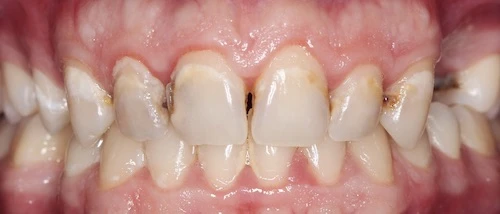

当由唾液不断形成的牙菌斑粘附在牙齿表面并且没有被充分清除时,问题就开始了。在这种情况下,牙菌斑和附着在其表面的数百万细菌会在我们口腔中的所有表面上形成厚厚的、有利于炎症的沉积物。在这种情况下,我们谈论的是牙龈炎症(牙龈炎)。右边是牙龈炎的图像。